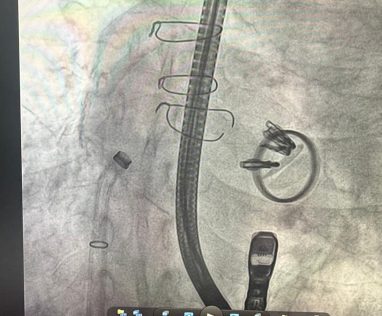

No dia 9 de outubro, foi realizado no Hospital Santa Izabel (HSI), procedimento de Reparo Borda a Borda da Válvula Tricúspide com colocação de clipes (TriClip), um dos primeiros realizados em Salvador. Trata-se de intervenção de alta complexidade, através do cateterismo cardíaco, sem cirurgia convencional, para o tratamento de insuficiência grave da válvula tricúspide. É indicado para pacientes que possuem alto risco cirúrgico e não melhoram com tratamento medicamentoso. Guiado por imagens avançadas de ecocardiograma e angiografia, o dispositivo é inserido através de uma veia da perna até a válvula tricúspide. A recuperação é rápida e promove melhora significativa da qualidade de vida do paciente. O procedimento foi comandado pelo cardiologista Dr. Adriano Dourado. Participaram também da equipe os médicos Dr. Joberto Sena e Dra. Angele Matoso.